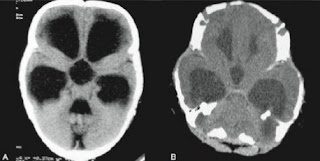

Ironicamente, apesar da maioria das premissas básicas da frenologia terem sido consideradas pseudociência, as leituras dos comportamentos e a sua relação com o crânio não foram. O princípio de que as funções específicas cerebrais estão localizadas em topografias determinadas é agora conhecimento comum demonstradas por técnicas modernas de imagem, como a ressonância magnética funcional (FMRI). Esta doutrina que possibilita a visualização precisa de uma determinada função quando ela está sendo realizada é chamada de localizacionismo cerebral.